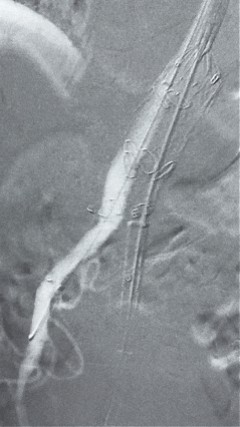

7. 经长鞘重新选入左侧外分支,并超选进左肾动脉,沿导丝送入外周血管覆膜支架7*60mm一枚,并予以球囊后扩张,手推造影显影良好。

17.gif

8. 从右侧股动脉入路送入腹主支架AB-24-12-110-S,近端重叠胸腹主动脉支架远端,调整好支架位置后释放。

9. 经左股动脉送入导丝导管,超选进腹主动脉支架短腿内,后沿导丝送入髂支,同理,右侧沿导丝送入髂支并释放,使用先健顺应性球囊后扩各支架连接处及支架近远端,最后通过预留导管向瘤腔注入人纤维蛋白粘合剂数支,造影显示分支通畅。

19.gif